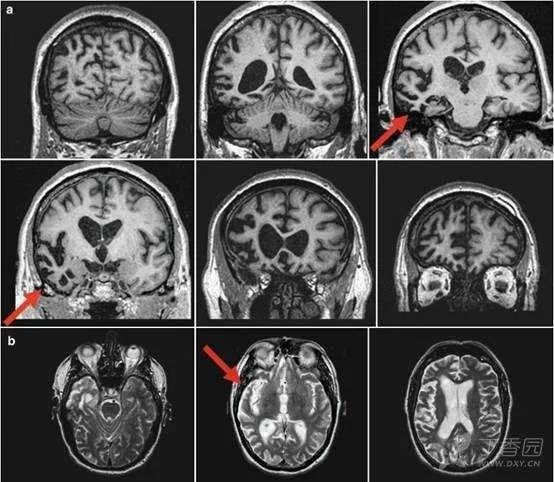

神经影像:颞叶t2wi/flair高信号病变的鉴别诊断

图片尺寸1078x574